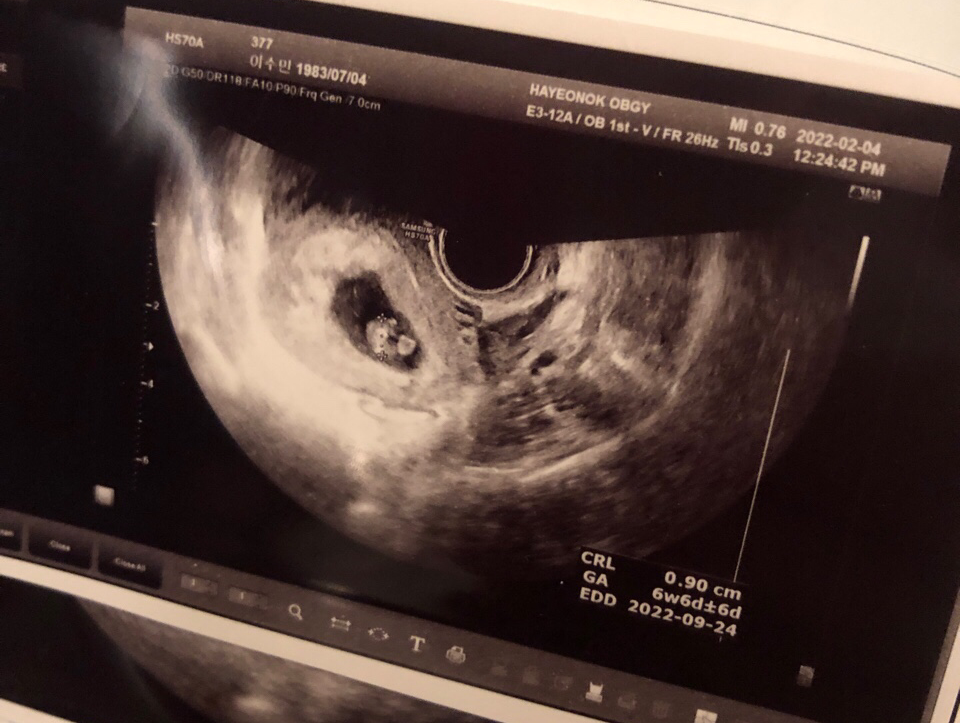

수련에서 수행으로 나아가는 지점엔 인생의 변화가 있었다. 업식의 변화가 일어나고 있구나 싶은 즈음 아기가 나에게 왔고 지금 내 곁엔 귀여운 아기가 브람스의 자장가를 들으며 자고 있다. 지금, 여기, 내 앞에 오는 이들에게 최선을 다하자는 마음으로 요가수련을 리드했는데 살아있는 아기는 전혀 다른 차원이었다. 우선 24시간 밀착케어였다. 에너지를 충전하고 정화하고 튜닝할 시간과 여유는 주어지지 않았다. 그냥 해야 했다. 에너지가 소진되어 제로 상태여도 아기는 내 사정을 봐줄 리 없었고 마치 좀비처럼 영혼 없이 움직이는 새벽의 나를 볼 때 이것이야 말로 수행이구나 싶었다.